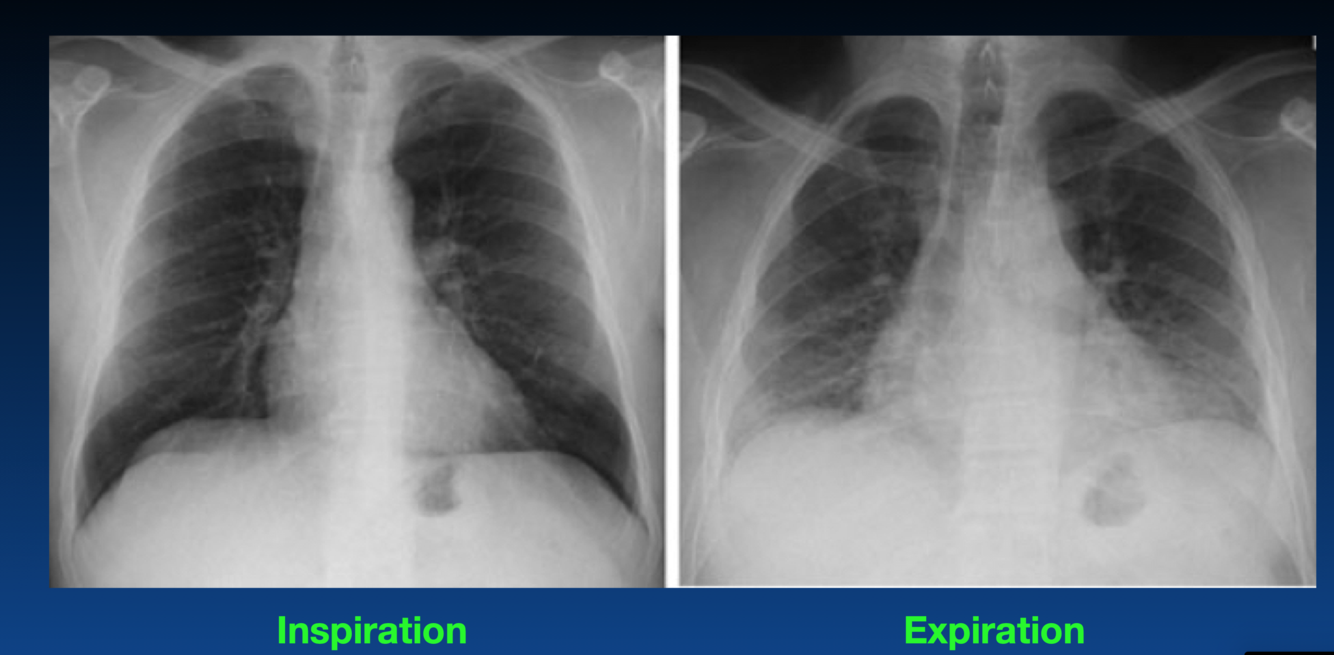

This does not show a real increase CTR. Why?

You can tell an expiration by the height of diaphragm as well as counting the ribs (the right only shows 4 ribs). You should see 6 or 7 ribs.